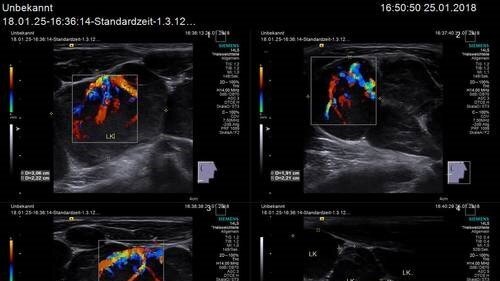

Die Aussagekraft des Ultraschalls kann erheblich durch die Anwendung des Dopplereffekts erhöht werden. Die sich in Gefäßen bewegenden Blutkörperchen können dann auf dem Bildschirm richtungsbestimmt farbkodiert wiedergegeben werden, was als Farbdopplersonografie bezeichnet wird. Verwendet man zusätzlich noch Kontrastmittel, wird die Durchblutung von Kapillaren sichtbar. Der Ultraschall ist das am häufigsten genutzte bildgebende Verfahren in der Medizin. Ein wesentlicher Vorteil gegenüber den in der Medizin ebenfalls häufig verwendeten Röntgenverfahren, wie etwa Computertomografie, liegt in der Unschädlichkeit der eingesetzten Schallwellen; diese sind sogar für Kinder und Schwangere völlig ungefährlich und schmerzfrei.